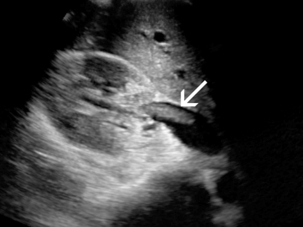

Диагноз РВТ основывается на обнаружении тромба, заполняющего почечную вену ( рис. 9-21 ), или неокклюзионного тромба, окруженного венозным потоком. В некоторых случаях вена может быть расширена тромбом. Отсутствие кровотока в почечной вене без признаков тромба может указывать на RVT; однако демонстрация низкого уровня цветового сигнала внутри вены при допплерографии не исключает возможности неокклюзионного или окклюзионного тромба почечной вены. Монофазные венозные волны являются аномальными, но не специфичными для RVT. Из-за возможности распространения тромба краниально в пределах НПВ ( рис. 9-22 ) и влияния на клиническое лечение, НПВ следует визуализировать в рамках сонографического исследования при оценке РВТ.

РИСУНОК 9-22 Тромб почечной вены. На изображении правой почечной вены в оттенках серого виден линейный тромб (стрелка), распространяющийся в НПВ. У этого пациента тромб был подвижным во время сердечной пульсации, что вызывало беспокойство по поводу возможной последующей эмболии.